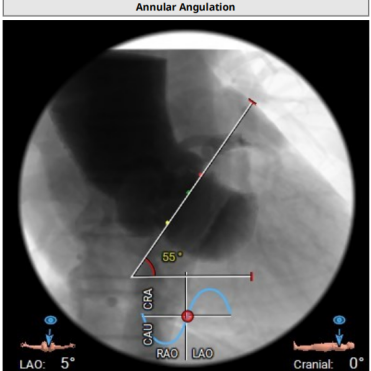

● 瓣环平面与水平夹角为55°,近横位心,主动脉弓夹角、弓距尚可;

● RAO18° CAU29°(左右重合位)左右跨瓣;

● 22mm球囊充分预扩,预扩角度LAO7° CRA3°(左冠切线位)左右;

● 预装AV26瓣膜,瓣环上2~4mm定位释放,释放角度RAO18° CAU29°(左右重合位)左右,释放后调整至左冠切线位LAO7° CRA3°左右进一步评估冠脉灌注、瓣膜稳定性及展开形态后释放;